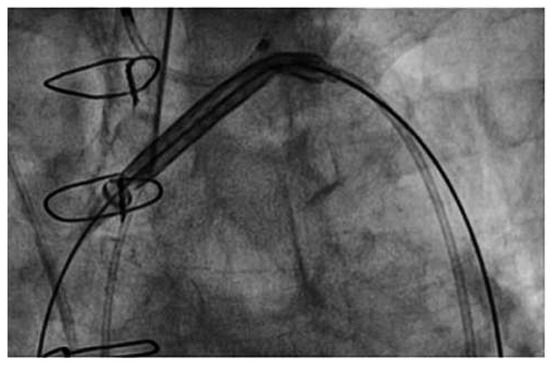

An 83-year-old man with ischaemic heart disease and a triple bypass in 2007 presented to the emergency department with increasing shortness of breath and weight gain of 5 kg over one month [...]